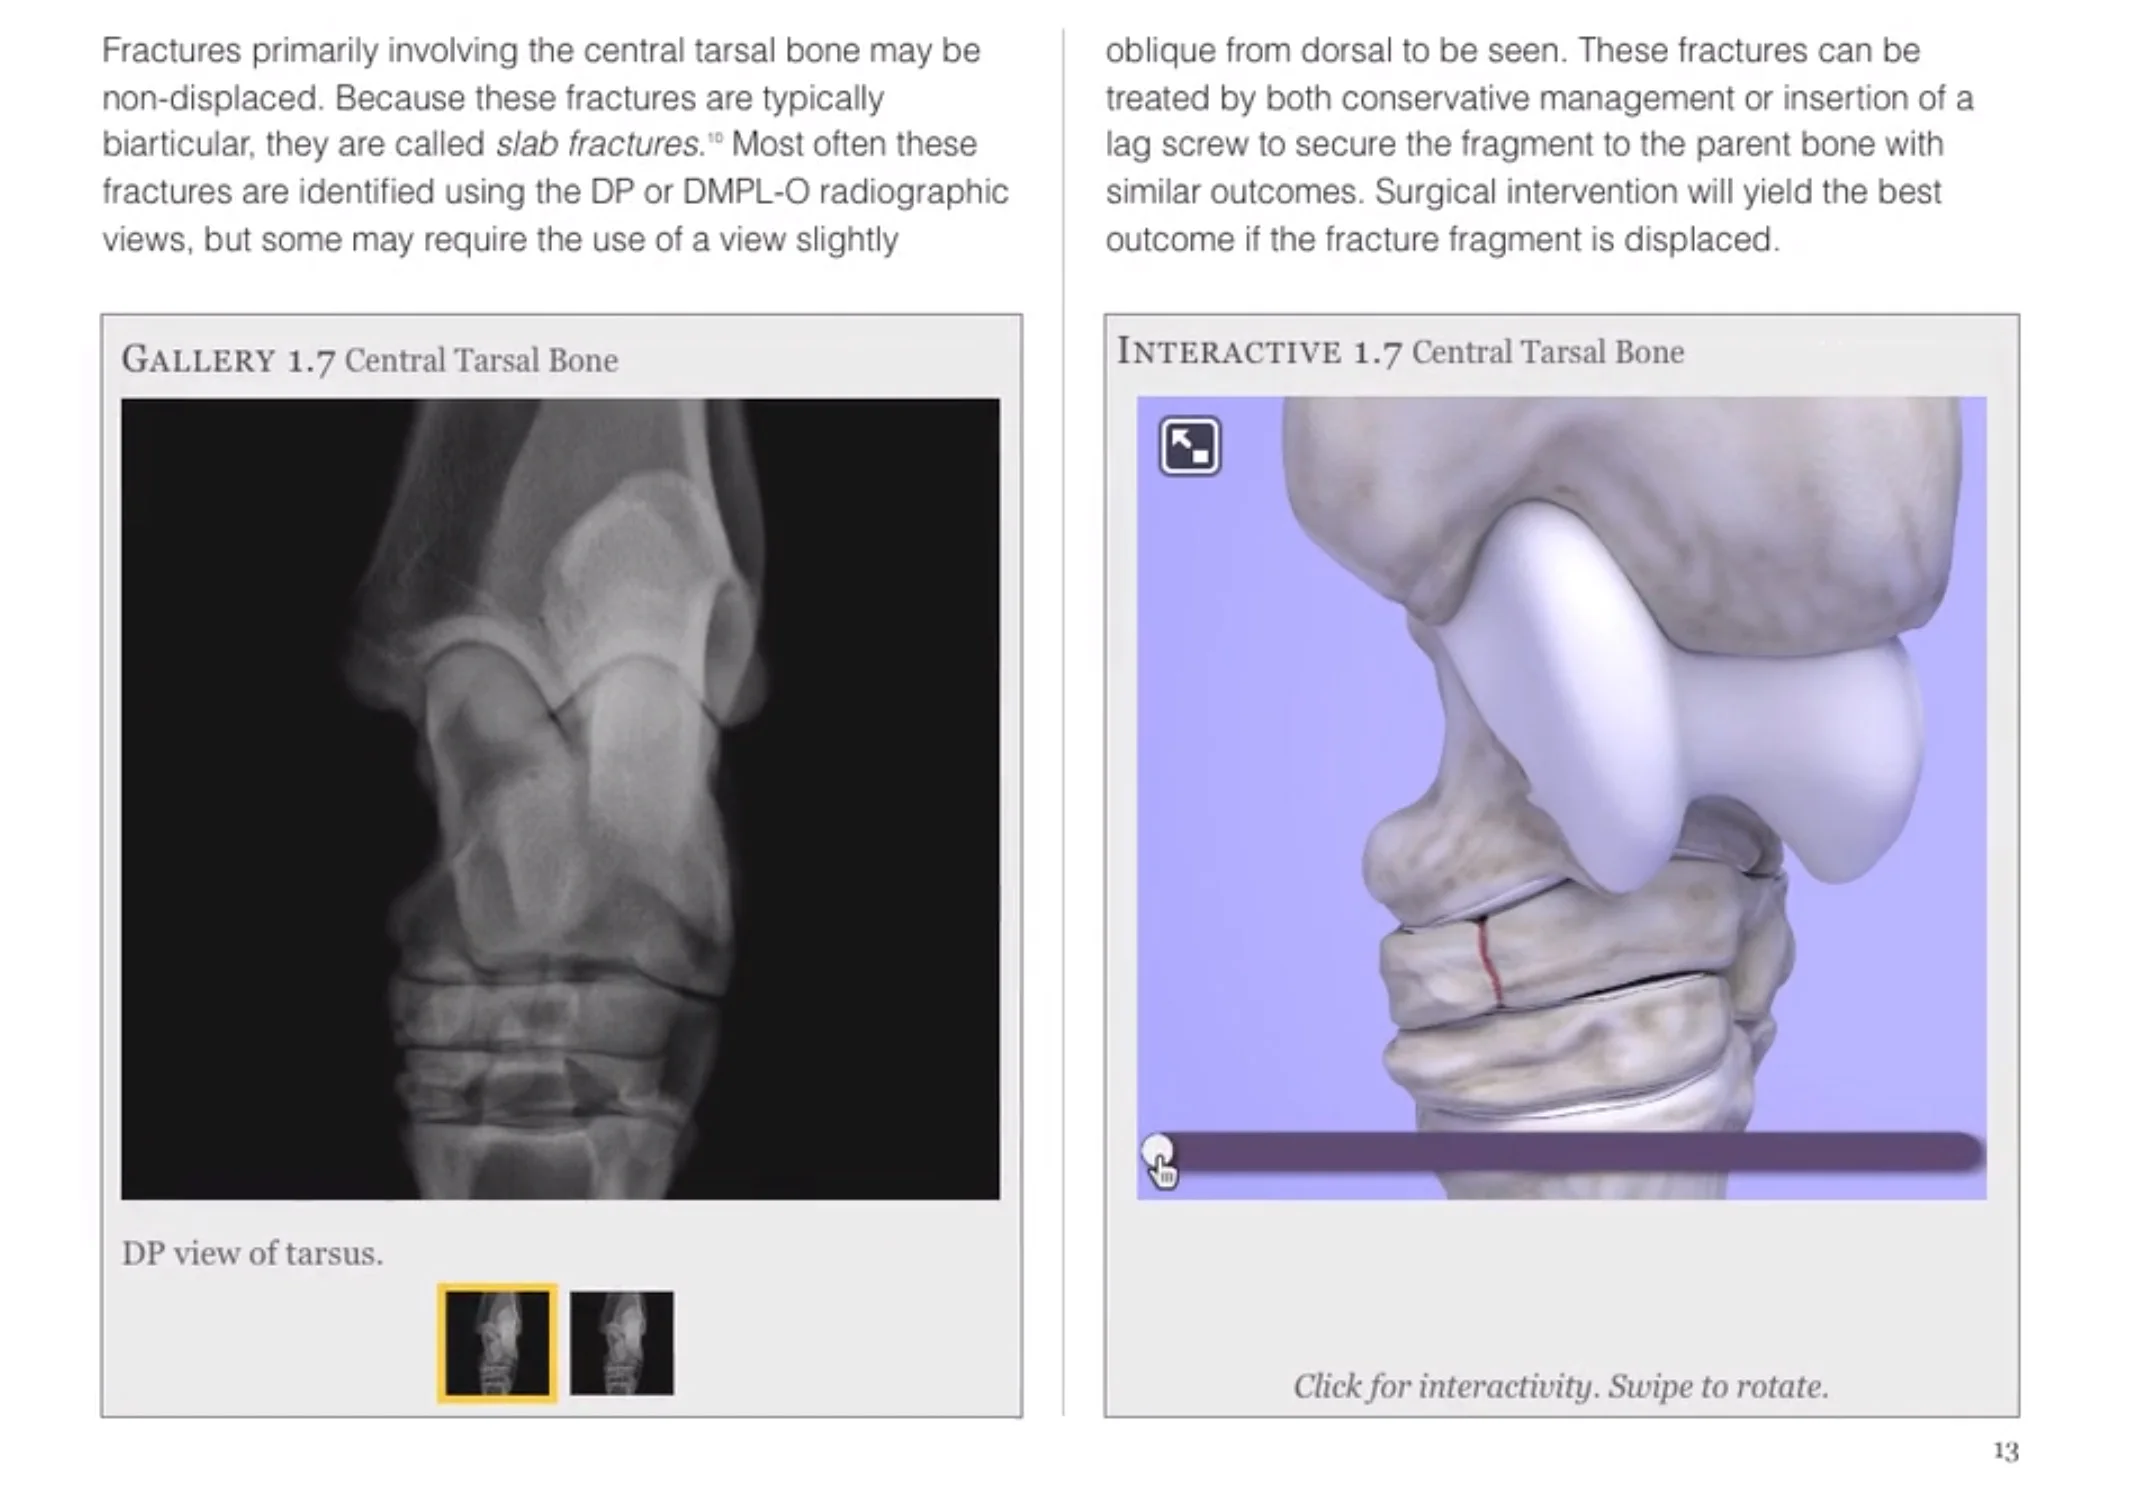

A short walkthrough of the various interactive widgets demonstrating common bony abnormalities of the equine tarsus.